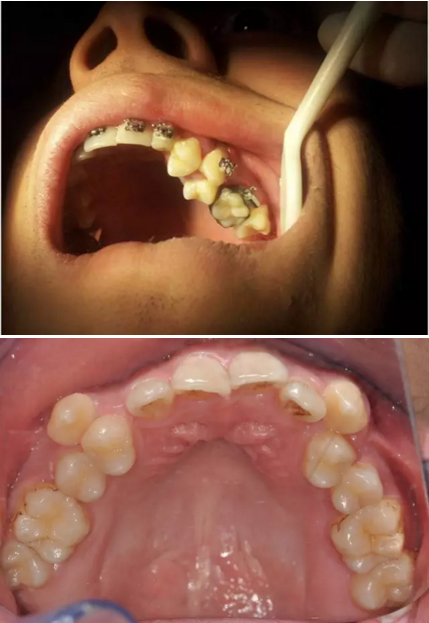

阻生齒外科聯(lián)合正畸治療

24.png

25.png

26.png

27.png

28.png